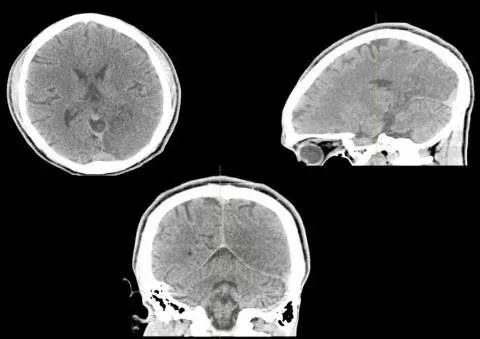

26岁,男,突发右眼视力障碍和精神状态改变入院。

11月后复查头部CT,如下图:

答案:线粒体脑肌病伴乳酸酸中毒及中风样发作(MELAS)

患者青年男性,卒中样起病,MRA未见明显异常,有好多老师想到静脉系统梗死,患者影像病灶并不符合静脉引流分布,答案是线粒体脑肌病伴乳酸酸中毒及中风样发作(MELAS)。其特征为轻度活动后即感疲乏无力,休息后好转;肌肉活检可见破碎红纤维。常以卒中样发作、痴呆、癫痫和共济失调等为主要表现。病灶影像特点与脑梗死类似,也可呈多发性、对称性、迁移性脑梗死样病变。皮层层状异常信号是其特征性影像表现。鉴别诊断有栓塞或夹层所致的真正的缺血性卒中、亚急性坏死性脑脊髓病(Leigh 脑病)、血管炎和癫痫等。